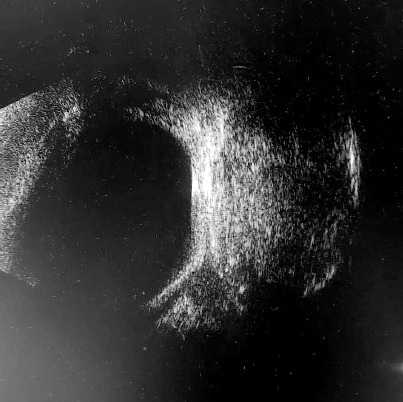

Examination revealed reduced visual acuity in the right eye (VOD) at 0.1 and intraocular pressure in both eyes measuring 7 mmHg. A physical examination of the right eye (OD) showed mixed ocular injection (Figure 1). Iris vascular dilation accompanied by posterior synechiae were observed. The cornea was hazy, and small punctate fluorescein-staining areas were observed in the lower hemisphere of its epithelium (likely resulting from the patient rubbing her painful eye). The lens was clear. Inflammatory cells were detected in the anterior chamber. The optical coherence tomography (OCT) scan of the macula was within normal limits. Due to limited visibility of the fundus, an ultrasound of the right eye was performed, revealing an oval hypoechoic mass in the orbit, measuring 17.95 mm × 11.35 mm. The lesion was located in the temporal region (Figure 2). Left eye (OS) examination revealed normal visual acuity, VOS 1.0. The anterior segment and fundus of the OS were within normal limits. For symptomatic management of anterior uveitis in the OD, topical dexamethasone and 1% tropicamide were administered, resulting in partial improvement. Due to significant anisometropia (refraction after 1% cyclopentolate-induced cycloplegia was +6.0 Dsph in the OD and +3.0 Dsph in the OS), the patient was prescribed spectacle correction (OD: +5.0 Dsph; OS: +2.0 Dsph). Ocular biometry revealed axial length discrepancy between OD (19.81 mm) and OS (21.18 mm).

For further evaluation, the patient was referred to the Department of Pediatric Hematology and Oncology at Karol Jonscher Clinical Hospital in Poznan with a diagnosis of iritis and a suspected orbital tumor . A contrast-enhanced magnetic resonance imaging (MRI) scan of the craniofacial region was performed, revealing a well-circumscribed, slightly heterogeneous tumor mass measuring 12 × 11 × 15 mm within the right orbital boundaries, in the area of the greater wing of the sphenoid bone. The lesion demonstrated no post-contrast enhancement and showed no diffusion restriction on DWI/ADC sequences (Figure 3). Orbital computed tomography (CT) revealed bone thinning likely caused by the tumor mass, along with segmental disruption of the orbital walls adjacent to the lesion (Figure 4). The radiological findings raised suspicion of malignancy, leading to a planned biopsy. However, intraoperatively, the tumor’s well-defined margins prompted a decision to proceed with complete tumor resection with the capsule. The subsequent histopathology examination confirmed the diagnosis of DC. Symptomatic treatment for right eye uveitis was continued.